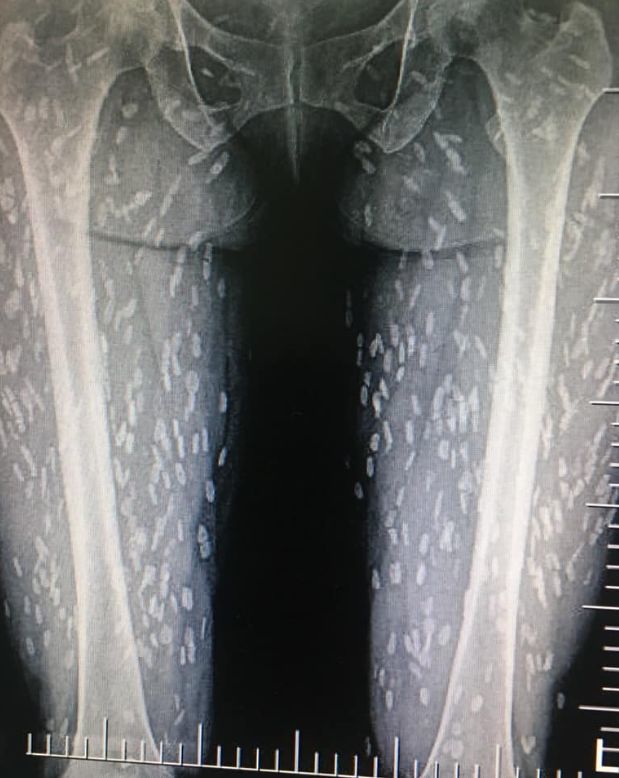

拍了x光片后,也可以看到密集的钙化的死亡的猪肉绦虫囊尾蚴

图片尺寸541x576

寄生虫就是想把机体当巢穴,不然怎么叫寄生虫?

图片尺寸495x587